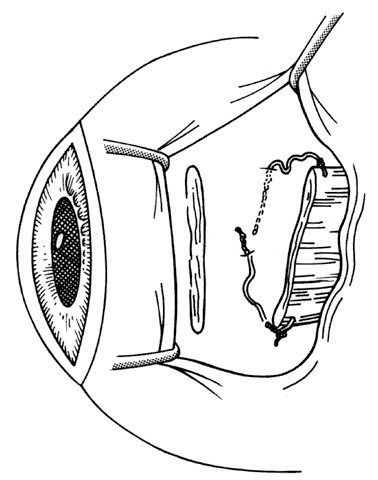

In patients with acquired sixth cranial nerve palsy, there may be a recurrence of esotropia, especially if there is minimal innervation of the lateral rectus. Creation of abducting force can be achieved by transposition of the vertical recti temporally by half of a muscle tendon width or more (Hummelscheim) or by use of a Jensen or similar plication procedure (see elsewhere in these volumes). When a full tendon transfer is performed, consideration should be given to preservation of the anterior ciliary vessels in the vertical recti. The undesirable occurrence of hypertropia when using a full tendon transfer of the vertical recti may be controlled with the use of adjustable sutures.

Reintervention to correct strabismus is indicated if a technical problem occurred immediately after the initial procedure. A muscle that has become disinserted or is “lost” postoperatively requires immediate exploration and correction of the problem (Figs. 2 and 3). A similar situation may occur when a previously operated muscle retracts ("slips") inside the muscle capsule (Fig. 4). The slipped muscle will appear paretic, and early surgical intervention should be considered. The clinical pictures of these technical failures are very similar. There is poor function of the affected rectus muscle, and the induced strabismus will be noncomitant. Operations may be performed on the incorrect eye muscles or eye (Fig. 5). If this occurs, reoperation should not be delayed.